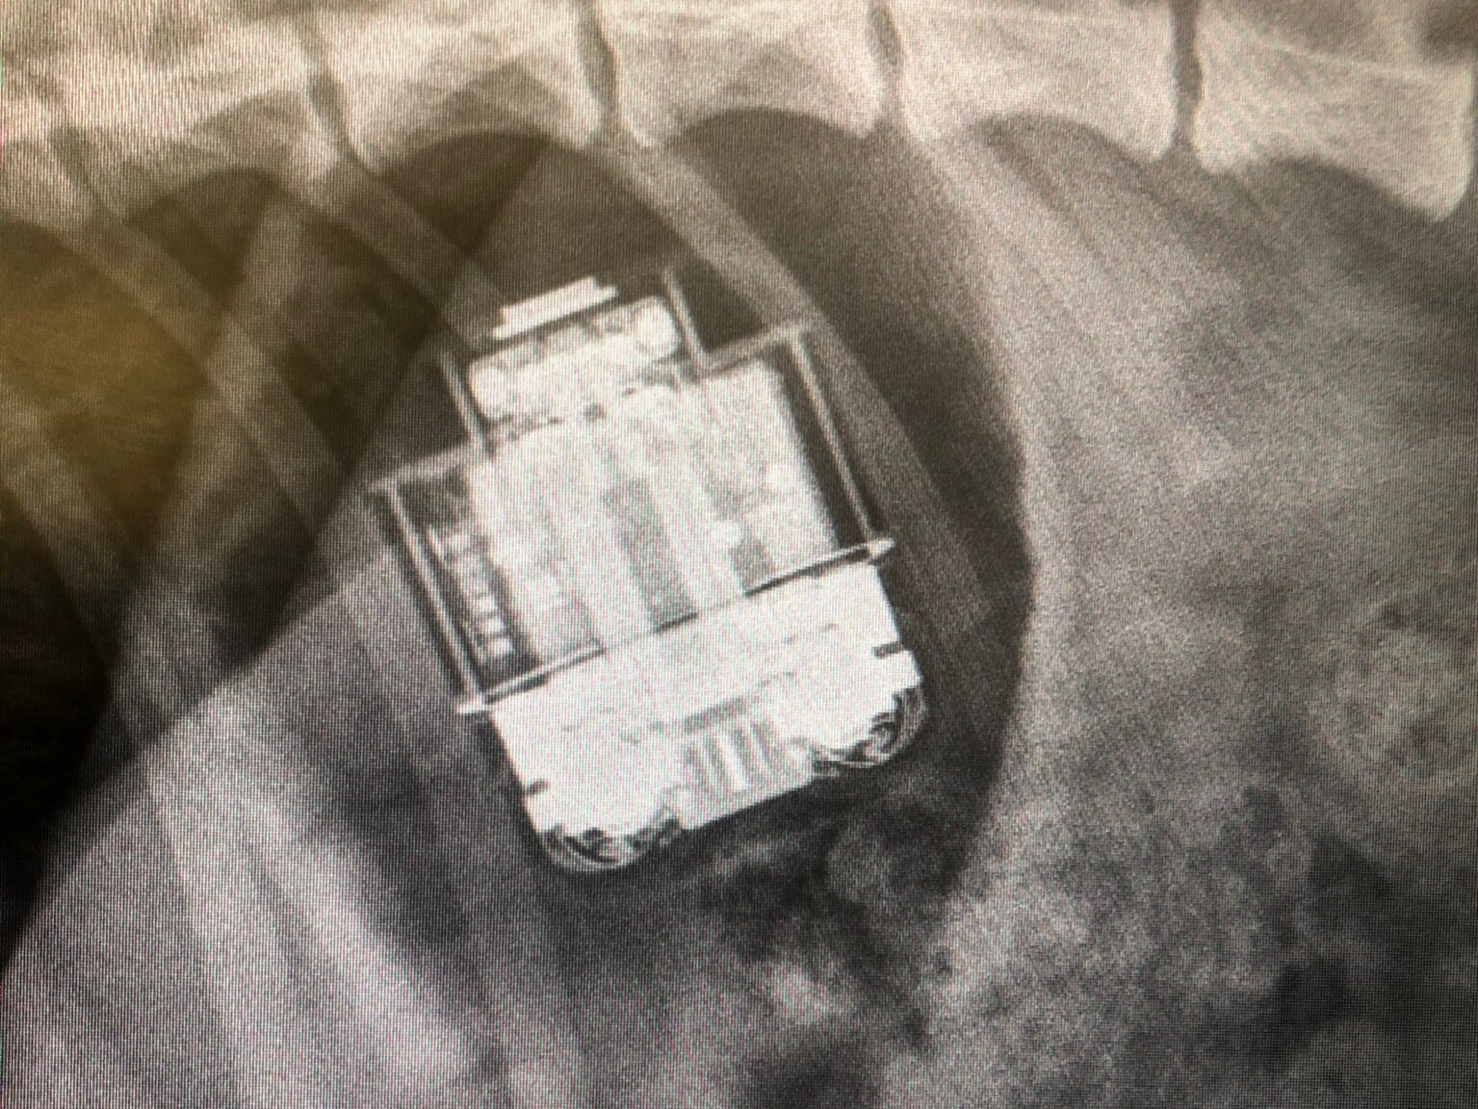

うーん放電も試してみたけど画面スリープ後はやっぱりこんな感じになるんだよな…USB-Cで接続してるけど、接続方法とか設定でまた違うのかな…モニタの電源入れ直すと一旦は直るけどスリープするたびにこんな感じになる…DDPM消すとこんなことにはならないから原因はDDPMなんだけど…